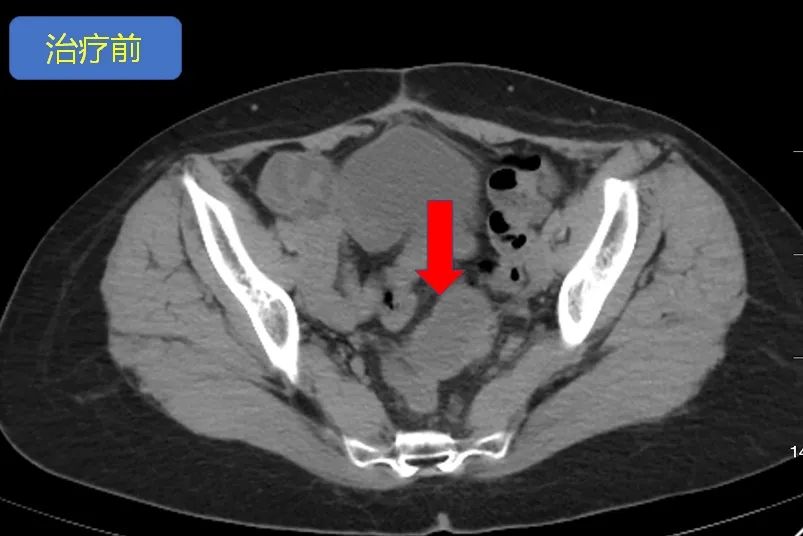

△PD-1抗体治疗前

但好景不长,2018年6月,复查肿块再次增大(图1所示)。同时,由于药物副作用引起的手足综合症(一种皮肤毒性,肿瘤患者在接受化疗或分子靶向治疗的过程中可出现。),疼痛、红斑、肿胀的情况加重,张女士不得已停用了阿帕替尼,治疗陷入僵局。